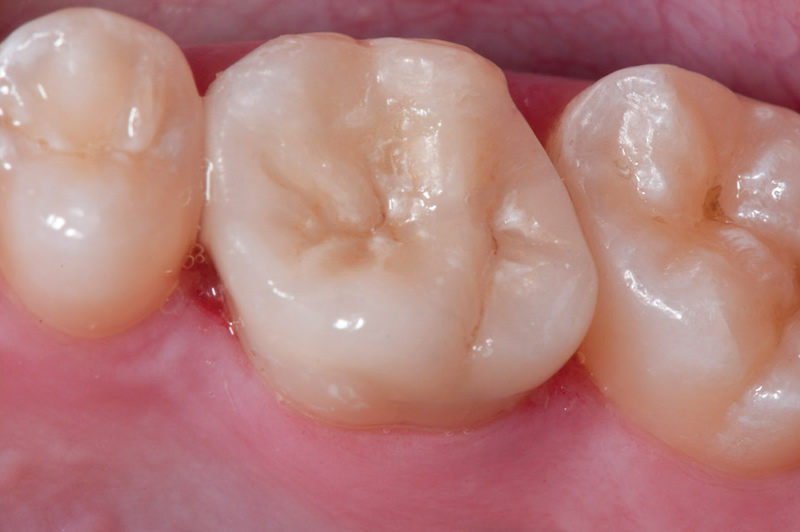

Fig 11. Preoperative view (Fig 9), preparation with composite block-out restoration (Fig 10), and final cementation of CL-IIb material (Fig 11) (final ceramic contour and stain by Steve Lee, CDT, MDC).

Figure 11